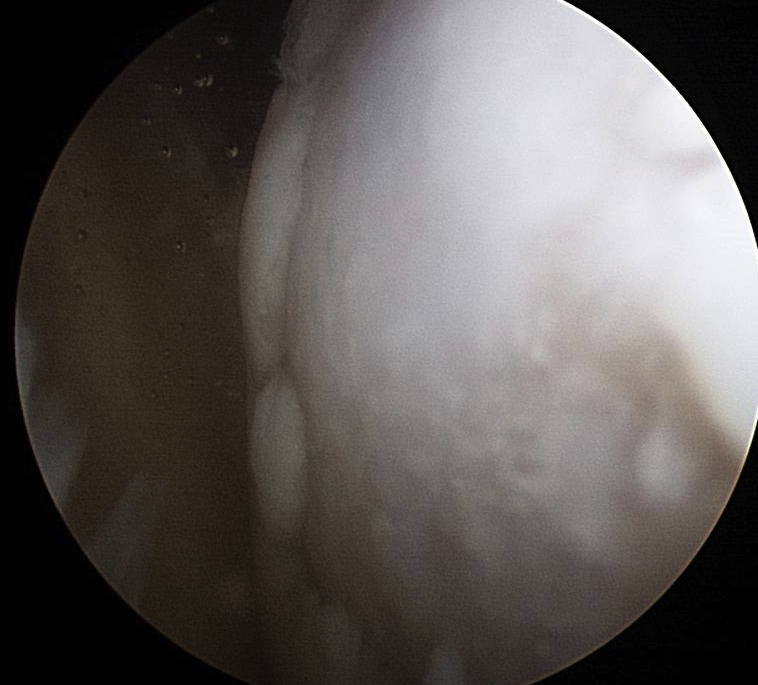

Three thickenings of the glenoid capsule: SGHL, MGHL, IGHL

| Superior glenohumeral ligament (SHGL) | Middle glenohumeral ligament (MGHL) |

|---|---|

|

Origin: Supraglenoid tubercle glenoid and coracoid Insertion: Proximal aspect medial edge lesser tuberosity of the humerus |

Origin: Distal aspect lesser tuberosity of humerus Insertion: Posterior aspect subscapularis |

Runs perpendicular to the middle GHL |

Crosses subscapularis vertically Variable size and shape in different people Cord like / leaf like / vestigal |

Stabilizes the long head of the biceps in its groove Limits external rotation of the humerus |

Limits external rotation with arm by side |